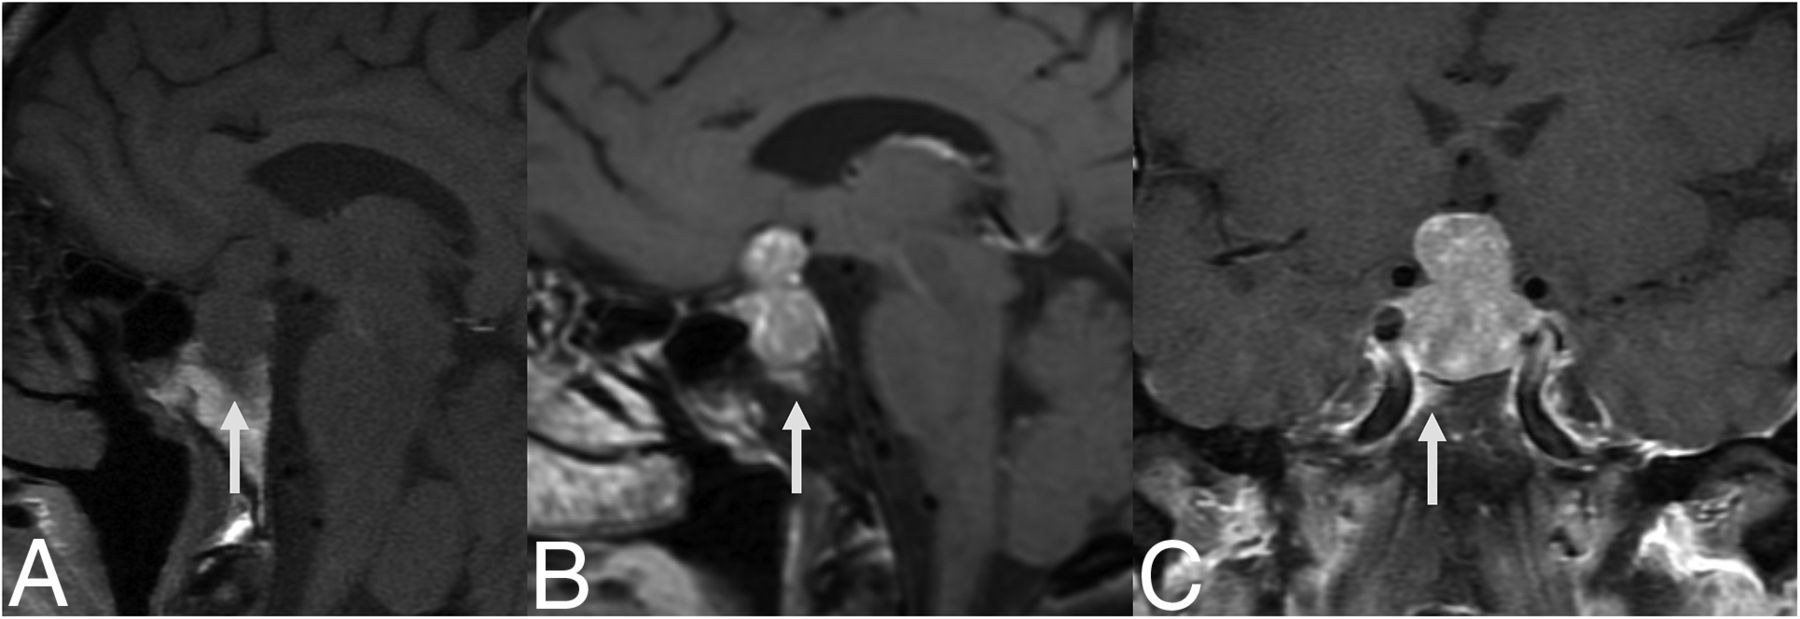

A 51-year-old woman presented to an outside institution with headache, dizziness, hyponatremia (113 mEq/L), and emesis with 11 kg of unintentional weight loss (Fig 2). Her laboratory values were consistent with central hypothyroidism, and she was treated with levothyroxine. The contrast-enhanced MRI showed a 1.8-cm sellar mass with type 3 pneumatization of the sphenoid sinus and enhancing bone marrow edema of the basisphenoid. The diffuse enhancement spanned nearly the entire anterior-posterior and transverse dimensions of the bone marrow beneath the sella. She was thought to have a pituitary macroadenoma and underwent endoscopic transsphenoidal resection of the central pituitary gland. The pathology demonstrated GH. Staining for acid-fast Bacillus was negative. She did not have a history of systemic granulomatous disease, and her pituitary lesion was thought to represent primary, idiopathic GH.

MR images of patient 1 with idiopathic GH and type 3 (sellar) sphenoid sinus pneumatization. Precontrast T1-weighted sagittal image (A) shows low signal in the infrasellar basisphenoid bone marrow. This low signal corresponds to bone marrow enhancement below the sella (arrows) seen on sagittal (B) and coronal (C) T1-weighted fat-saturated postcontrast images.